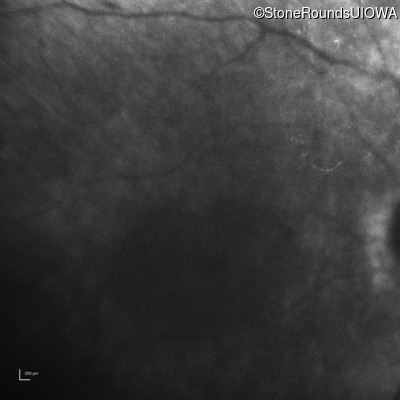

Infrared Fundus Photograph - Left - No Light Perception

Exemplar